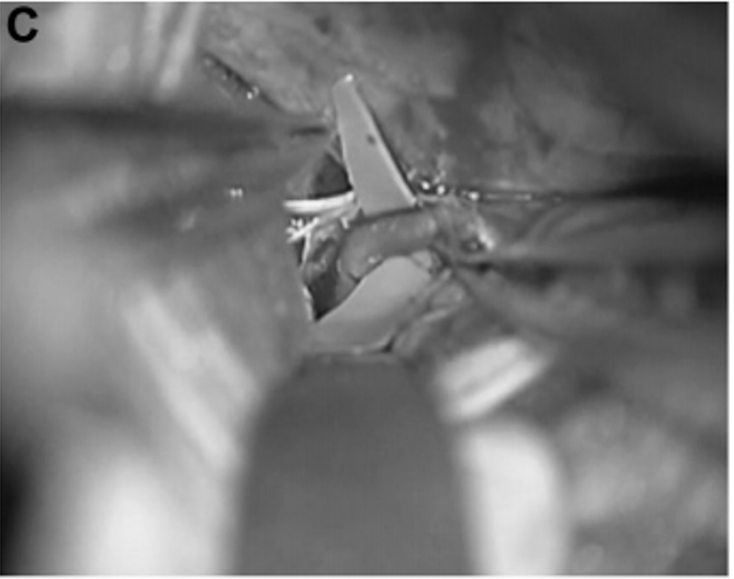

为了夹住动脉瘤,川岛教授使用了直长夹和有孔夹的组合,以避免 P3 段和 PTA 扭结。

P3 段被选为搭桥血管位置(图 2C 和 2D)